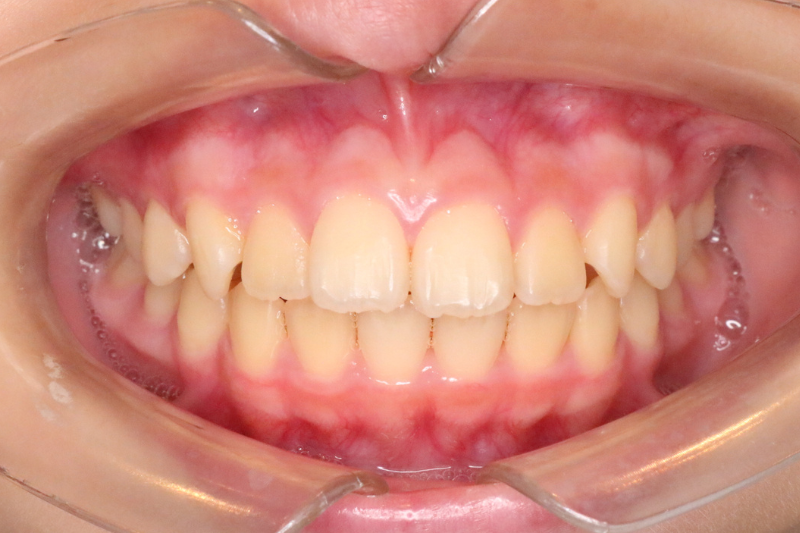

症例4

Before

症例4 治療前

After

症例4 治療後

年齢・性別 10歳・女の子

治療内容 インビザラインファースト

治療期間 1年7ヶ月

費用 400,000円(税込)

主なリスク 矯正装置の装着時に違和感や痛みが生じる場合があります。

装置の使用状況により治療期間が延長する場合があります。

治療後、保定装置を使用しない場合は後戻りする可能性があります。

治療結果には個人差があります。